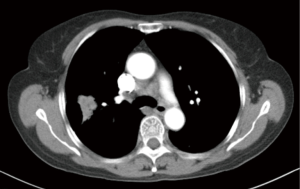

A patient, female, 61 years old, was discovered with a space-occupying lesion on the right upper lung (Figures 1,2) during the routine physical examination. She has no past medical history (PMH) of long-term chronic diseases. After knowing that this mass might be lung cancer, the patient refused aspiration biopsy and asked for a thoracoscopic exploratory surgery.